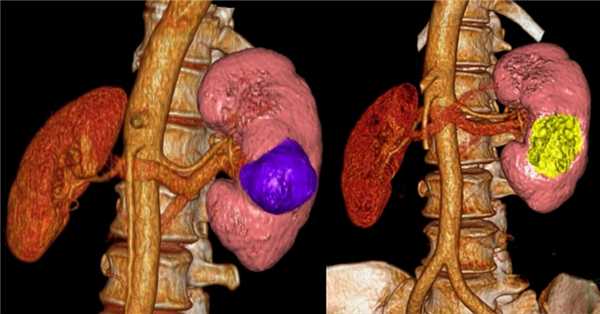

В зависимости от стадии и расположения опухоли, хирургическим методом может быть удалена только опухоль с окружающей частью почки — так называемая резекция почки, либо целая почка с опухолью — нефрэктомия. Надпочечниковая железа и жировая ткань вокруг почки также может быть удалена вместе с почкой, если возникнет необходимость.

Резекция почки

В ходе данной процедуры, хирург удаляет только ту часть почки, которая содержит опухоль, оставляя оставшуюся ткань почки неповрежденной. В настоящий момент это предпочтительный метод лечения для пациентов с ранней стадией рака почки. Часто резекции вполне достаточно для удаления одиночных небольших опухолей до 4 см в диаметре.

Также этот метод может применяться у пациентов с бОльшими образованиями, до 7 см. Специалистами НИИ онкологии им. Н.Н. Петрова успешно выполнялись вмешательства на опухолях размерами 10 и более см, однако такие операции возможны только в отдельных случаях, с учетом анатомии опухоли.